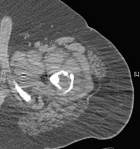

20 year old male presents after transfer to BGH with subtrochanteric left femur fracture

Zoom image: Radiological image Radiological image.